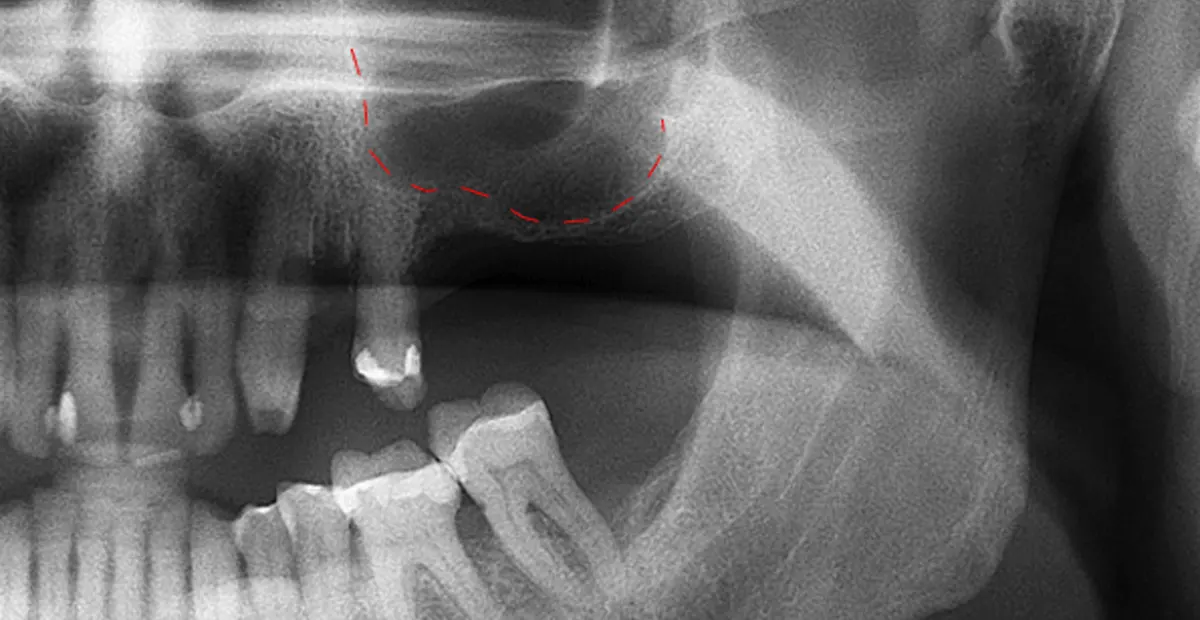

برخی افراد متقاضی کاشت ایمپلنت دندان در فک بالا با معضل کاهش تراکم استخوانی در نزدیکی دیواره سینوسهای صورت مواجهاند.. در واقع این امکان وجود دارد که مدت زیادی از کشیده شدن دندانها آن ها سپری شده باشد و به مرور زمان تحلیل استخوان رخ داده باشد به طوری که کاشت ایمپلنت می تواند با آسیب به حفره سینوس ماگزیلاری همراه باشد. افرادی که این مشکل را تجربه میکنند پیش از انجام جراحی کاشت ایمپلنت میبایست جراحی لیفت سینوس را انجام دهند.

زمانی که فک بالا فاقد ارتفاع و تراکم استخوانی کافی برای حمایت از کاشت ایمپلنتهای دندانی باشد، عمل لیفت سینوس ضروری میشود. در واقع علت اصلی ضرورت این عمل ناکافی بودن تراکم استخوانی در زیر حفره سینوس است و اگر این عمل انجام نشود کاشت ایمپلنت می تواند با سوراخ کردن دیواره سینوس و شکست ایمپلنت همراه شود.

قبل از انجام عمل لیفت سینوس، داشتن آمادگی کامل یک امر ضروری است. دندانپزشک شما، برای ارزیابی کامل میزان تراکم استخوان، وضعیت سینوسها و سلامت کلی دهان، اقدامات لازم را انجام خواهد داد. برای این ارزیابی ممکن است نیاز به گرفتن گرافی با اشعه ایکس یا سی تی اسکن باشد. علاوه بر این، یک گفتگوی مفصل برای رسیدگی به هر گونه نگرانی، توضیح روشهای جراحی، و تشریح نتایج مورد انتظار و خطرات بالقوه پیرامون لیفت سینوس انجام خواهد شد.